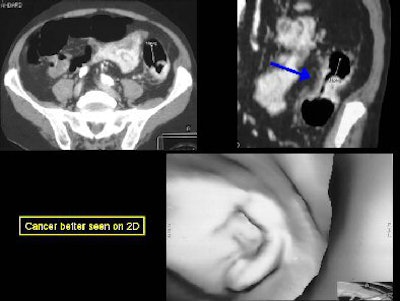

"Annular carcinomas are better evaluated on 2D views, and may be mistaken for an area of collapse on 3D," Yee wrote in her abstract.